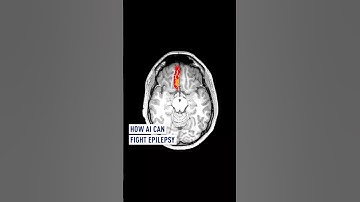

AI algorithm to detect brain abnormalities and help cure epilepsy